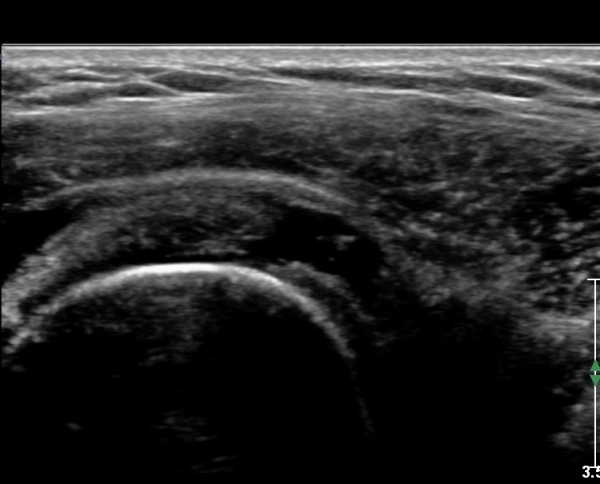

Å½ÃËÀÚ¸¦ Á»´õ ¸»´ÜÀ¸·Î À̵¿ ÈÄ(¶Ç´Â ¾Æ·¡·Î ±â¿ïÀÎ ÈÄ) ³»ÃøºÎ¸¦ Á¶ÀýÇÏ´Ï °ß°©ÇϱٰÇ

Ç¥ÃþÀ¸·Î Á¡¾×³¶³» ¼ö¾×Àú·ù°¡ °üÂûµÈ´Ù(»çÁö 3, 4). ŽÃËÀÚ¸¦ Á¶Á¤ÇÏ´Ï ÀÌµÎ¹Ú°Ç ÁÖÀ§ ¼ö¾× Àú·ù¿Í

Á¡¾×³¶³» ¼ö¾×Àú·ù°¡ °üÂûµÇ¾î Á¡¾×³¶¿°°ú Ȱ¾×¸·¿°ÀÌ ÀÖÀ½À» ¾Ë ¼ö ÀÖ´Ù(»çÁø 5).